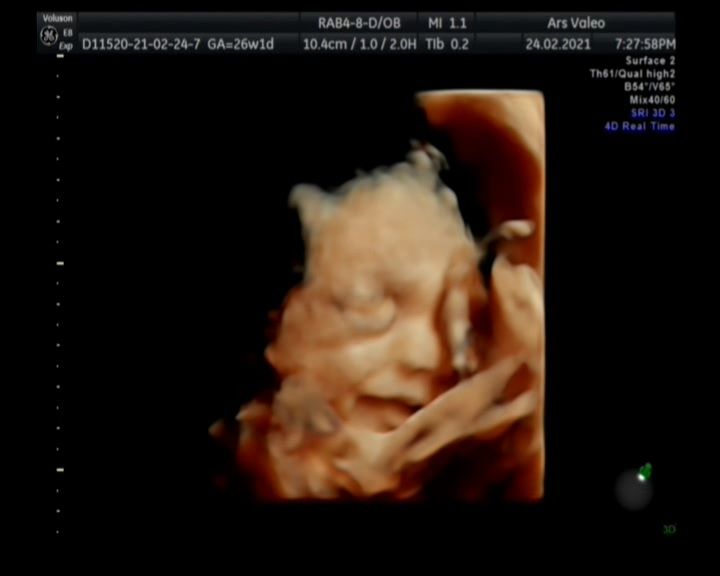

Фото узи с 26 недели. Мой маленький сладкий улыбашка😍